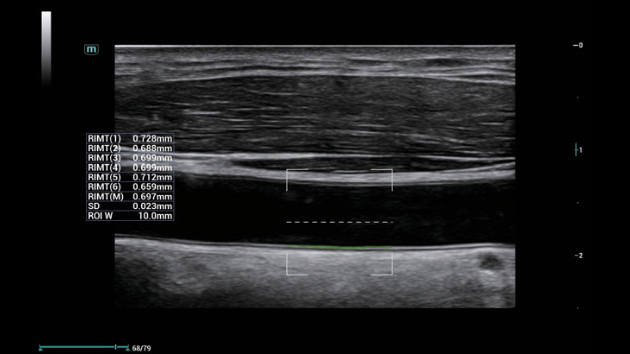

Solu??es abrangentes de imagens com tecnologia ZST+

A plataforma ZST+ ÃĐ uma inova??o extraordinÃĄria, representando a evolu??o do ultrassom. Transformando as mÃĐtricas de ultrassom: da forma??o convencional do feixe ao processamento baseado em dados de canais. Supera a limita??o de compensa??o tradicional entre resolu??o espacial, resolu??o temporal e uniformidade de tecido, oferecendo qualidade de imagem excepcional para solu??es de imagem infinitas com melhorias inigualÃĄveis.